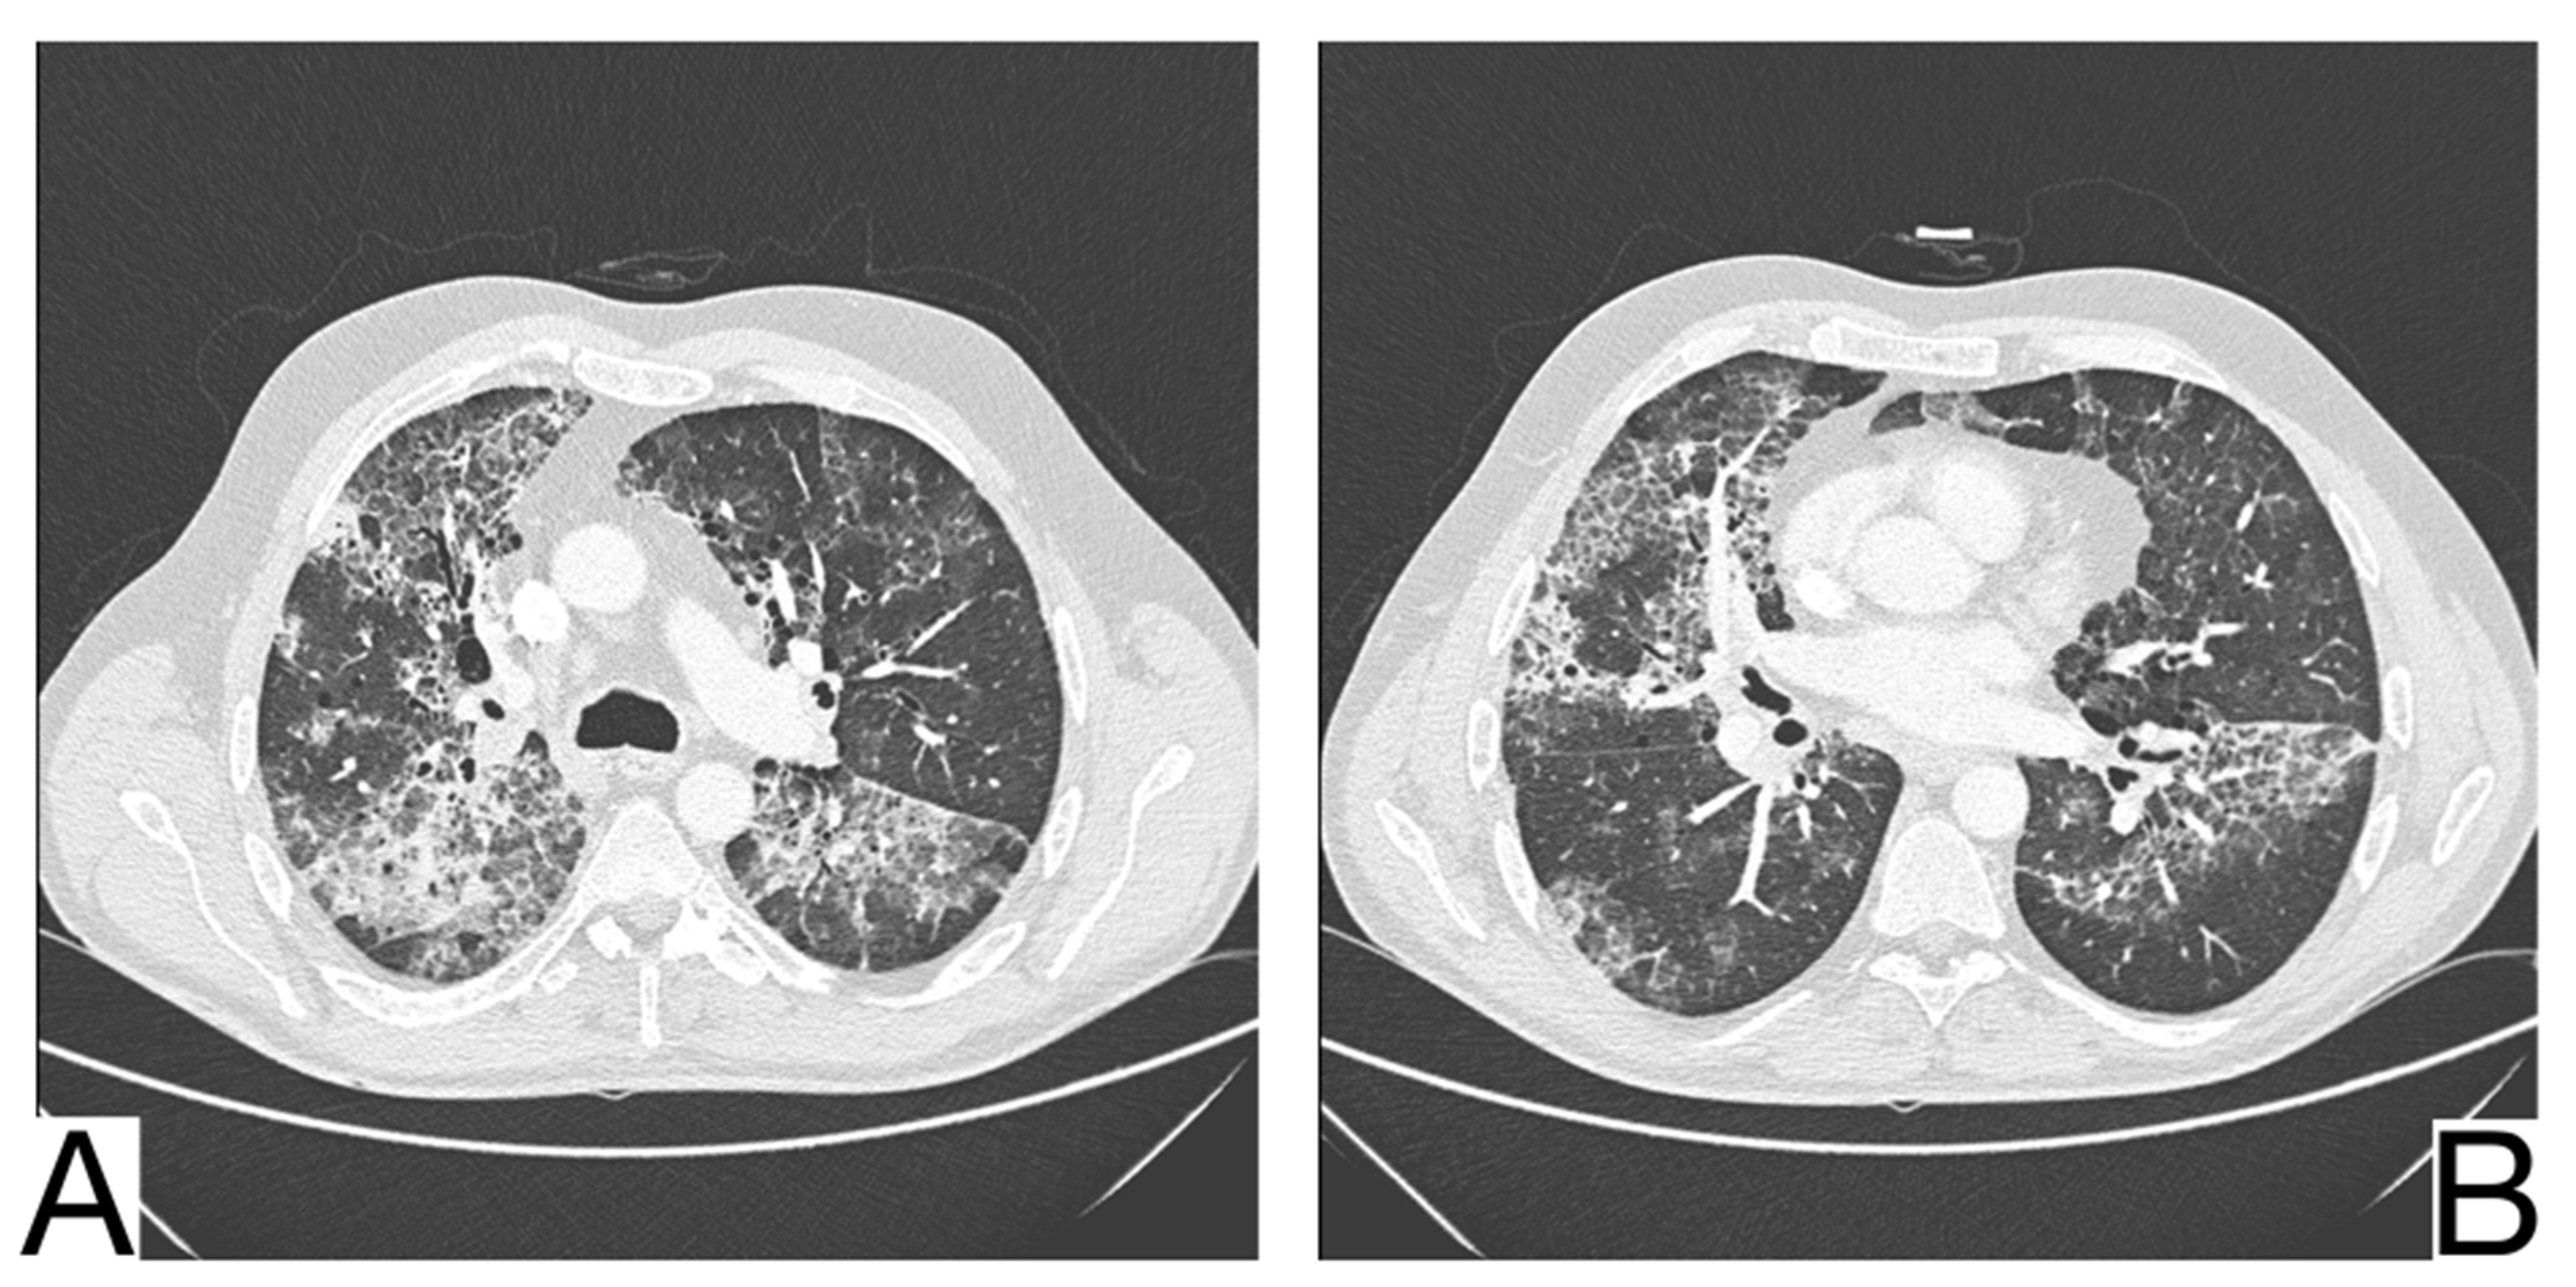

Imaging characteristics for differential diagnosis are (Figure 10A,B): the absence of the cobblestone in simple pulmonary eosinophilia (SPE), also known as Loeffler syndrome); pleural effusions, centrilobular nodules, and thickening of lar bundles in acute eosinophilic pneumonia []; centrolobular consolidations with occasional frosted glass and cobblestone opacities in chronic eosinophilic pneumonia; additional findings in chronic eosinophilic pneumonia are represented by nodules, atelectasis, band opacities, and pleural effusions [,].

Figure 10. Chronic eosinophilic pneumonia (A,B). Consolidation throughout both lungs. Note. Case courtesy of Dr. Henry Knipe, Radiopaedia.org, rID: 39331.